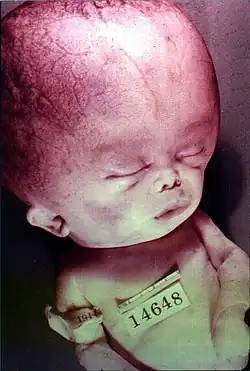

Hydrocephalus is difficult to detect clinically before delivery, although enlarged ventricles can be spotted on ultrasonography as early as 18–20 weeks gestation.[7] Since infants' skulls are not fully fused together at the cranial sutures yet, they have soft spots on their skulls known as open fontanelles.[8] This anatomic characteristic means that infants' skulls can visibly grow in size when cerebrospinal fluid accumulates. Therefore, infants with hydrocephalus may present with an enlarged skull (or rapid growth in skull size), bulging fontanelles, or separated cranial sutures.[8][9] Parents or physicians may also note that the infant is more irritable or tired than normal. Other symptoms include seizures, inability to look upwards ("sunset eyes" or "setting sun" sign), and pauses in breathing.[8][9] Infants may also present with lack of weight gain or failure to meet motor and developmental milestones.[10] Imaging can be done to confirm the suspected diagnosis of hydrocephalus. In infants, the open fontanelles allow for use of head ultrasonography. This allows pediatricians to minimize radiation exposure and come up with a diagnosis quickly.[8] If further information is needed, an MRI can be done.[7]

Congenital hydrocephalus is defined by the presence of excess CSF at birth. It occurs due to a combination of factors, especially genetic causes prior to birth (meaning the fetus may develop hydrocephalus in utero during fetal development). The genes involved in congenital hydrocephalus involve aqueduct defects, development of the central nervous system, and cilia (involved in the movement and flow of CSF).[23] The most common cause of congenital hydrocephalus is aqueductal stenosis, which occurs when the narrow passage between the third and fourth ventricles in the brain is blocked or too narrow to allow sufficient cerebral spinal fluid to drain. Fluid accumulates in the upper ventricles, causing build up and hydrocephalus.[24]

Mechanism of symptoms

When the cerebrospinal fluid builds up, it causes compression of the brain, which leads to the symptoms of convulsions, intellectual disability, and epileptic seizures. These signs occur sooner in adults because their skulls are no longer able to expand to based on the increasing fluid volume. Fetuses, infants, and young children with hydrocephalus have head enlargement, excluding the face, because the pressure of the fluid causes the individual skull bones—which have yet to fuse—to bulge outward at their juncture points.[39]